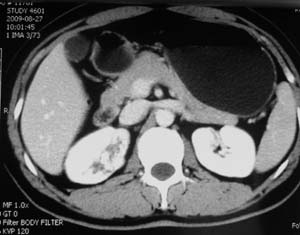

以下是引用子期在2010-3-19 20:47:00的发言:[br]血管畸形的ct增强应该有明显强化,本例并不相符合。本例双肾局部的略低密度影,累及肾盂,局部皮质明显变薄、内陷,增强扫描有轻度的强化,应考虑为炎性病变,患者为年轻男性,累及双肾的感染以结核较常见,可以没有明显的临床症状,尿中有时候也并不能查出什么;肾脓肿常有明显感染中毒症状,本例不符,另外一般的肾盂肾炎或肾小球肾炎通过小便就可确诊,其它还不能排除的是黄色肉芽肿性肾盂肾炎,然而单凭ct一般也很难鉴别。